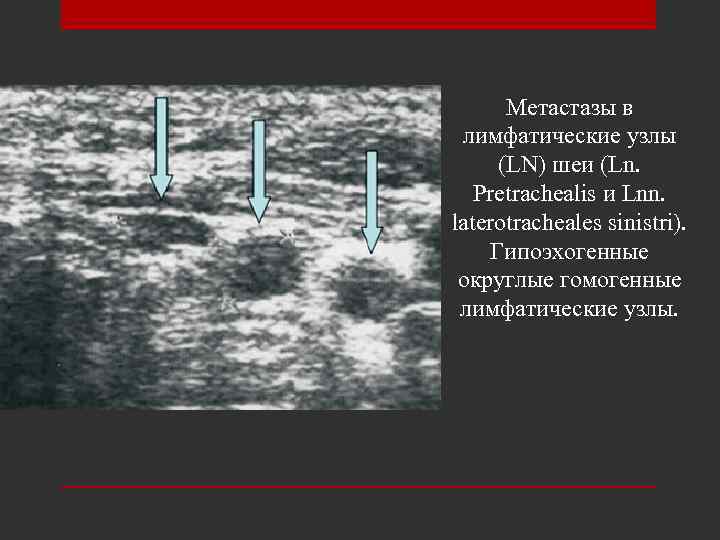

Метастазы в лимфатические узлы (LN) шеи (Ln. Рretrachealis и Lnn. laterotracheales sinistri). Гипоэхогенные округлые гомогенные лимфатические узлы.